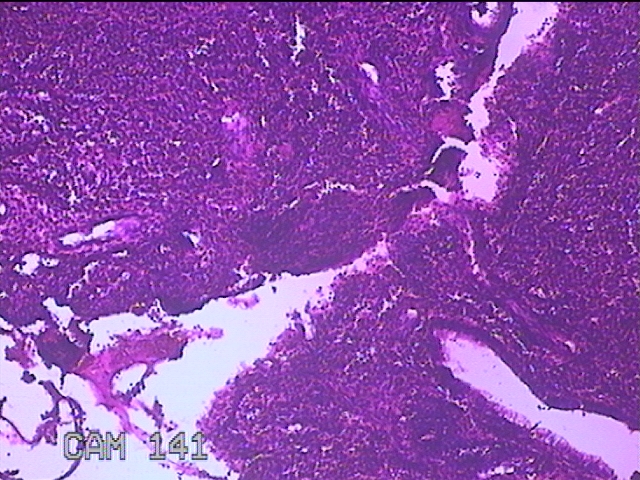

宫腔内容物

性别

女

年龄

42岁

临床诊断

异常子宫出血 取出子宫节育器

一般病史

月经紊乱2年,不规则阴道流血3月。

标本名称

大体所见

灰白暗红色不规则碎组织3.5x3x0.7cm一堆。